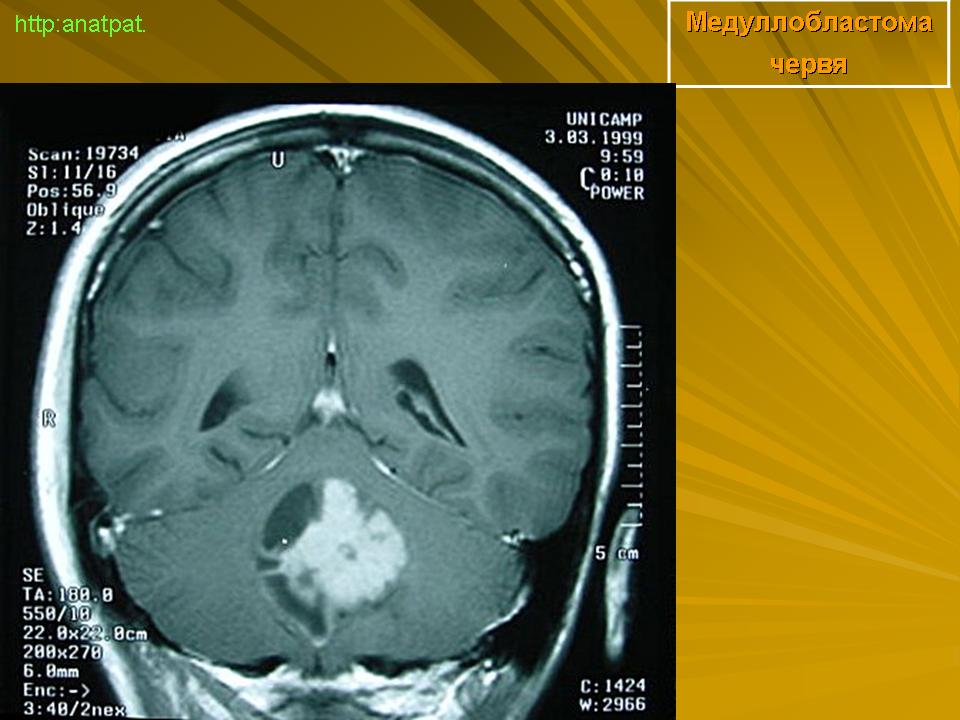

Медуллобластома - это опухоль, которая возникает из примитивных и эмбриональных клеток ЦНС. Локализируется исключительно в мозжечке и представляет 15-20% от детских опухолей мозга. 20% медуллобластом появляется в зрелом возрасте.

Это быстро растущая опухоль, очень злокачественна, имеющая тенденцию распространяться вдоль путей движения ликвора.

Вследствие локализации в мозжечке, обструкция путей циркуляции ликвора является достаточно частой и ранней, с последующей гидроцефалией. Синдром повышенного внутричерепного давления наряду с расстройствами равновесия, являются наиболее частыми и ранними признаками и симптомами.

Хирургическое лечение состоит в «радикальном» удалении опухоли, с последующей лучевой и химиотерапией, на которые медуллобластома часто очень чувствительна.

Результаты, с применением методов лучевой терапии и самыми современными схемами химиотерапии, достаточно хорошие. В настоящее время существуют больные прожившие уже более 10 лет после первой операции.